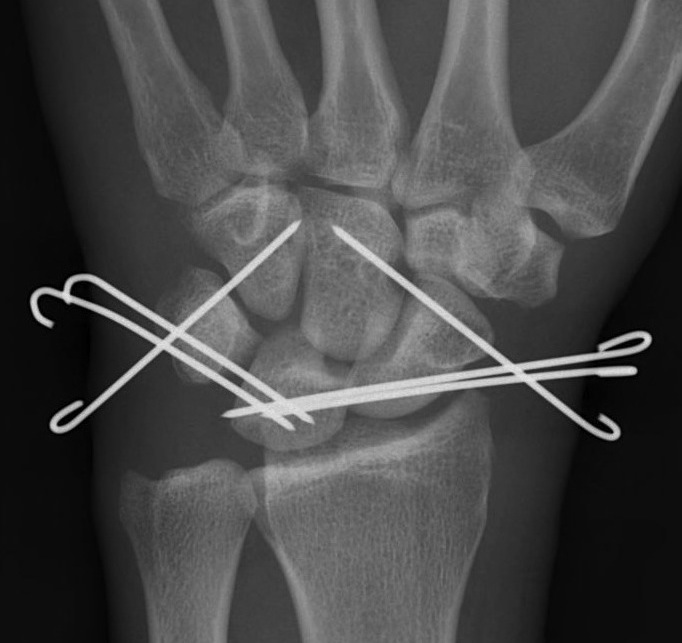

Perilunate dislocation / No scaphoid fracture

Technique

Dorsal approach

- 3/4 extensor compartment

- mobilise EPL laterally

- capsulotomy: T shaped or Berger (open dorsal between DRC and DIC ligaments)

- K wire joysticks in scaphoid and lunate and reduce

- K wires scaphocapitate / scapholunate / lunatetriquetral (areas of ligament rupture)

- +/- repair SL ligament if avulsed from scaphoid or lunate

- +/- repair LT ligament

- +/- reconstruction / internal brace SL and or LT ligament

- +/- SL screw

- +/- capsulodesis / tenodesis